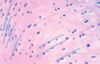

What layer of hyaline cartilage contains fibroblasts and produces type I collagen and elastin?

Outer fibrous layer

What layer of hyaline cartilage gives rise to chondroblasts and osteoprogenitor cells and contains chondroblasts secreting type II collagen?

Inner chondrogenic layer